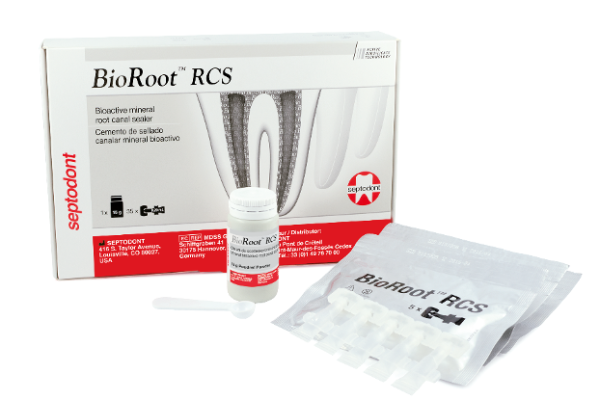

Why is Bioroot RCS changing the way dentists do root canal treatments?

What if you didn’t need to compromise between long term clinical success and an easy, fast technique when it comes…

Bioroot RCS – is a paradigm shift for root canal obturation possible?

Josette Camilleri discusses the composition and properties of the use of Bioroot RCS as a root canal sealer. Introduction The…